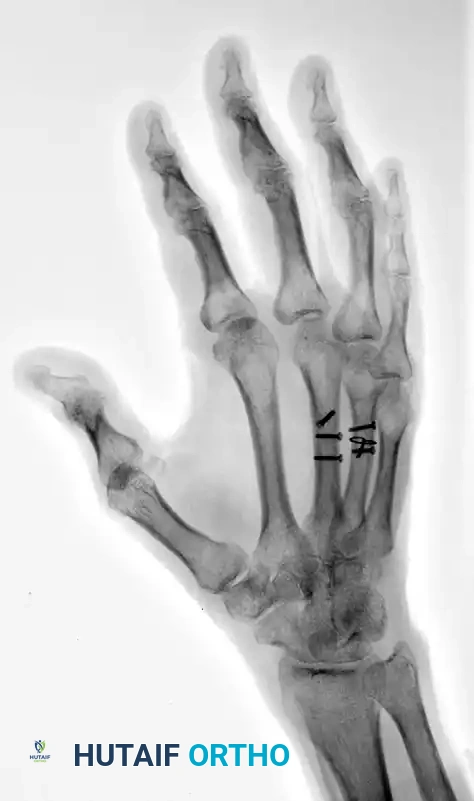

The following radiographs demonstrate a complex, three-part displaced intra-articular fracture of the proximal phalanx in a 27-year-old man. The articular surface is significantly disrupted, necessitating open reduction.

FIGURE 67-41 A: Preoperative anteroposterior radiograph demonstrating the intra-articular split.

FIGURE 67-41 B: Preoperative oblique radiograph highlighting the displacement and articular step-off.

FIGURE 67-41 C: Preoperative lateral radiograph showing the volar subluxation tendency.